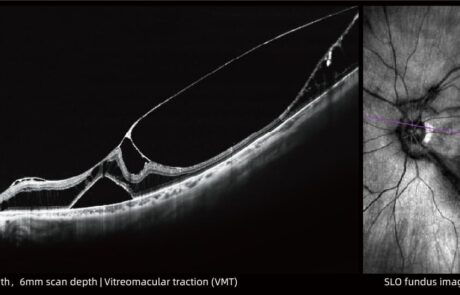

400KHz Ultra-Widefield

Full-Range SS-OCTA

Das TowardPi OCT-System ist das weltweit erste 400-kHz-Ultraweitwinkel-Vollbereichs-SS-OCTA mit vollständig eigenentwickelten Kernkomponenten.

Es ermöglicht eine 120°-Ultraweitwinkel Aufnahme in nur 7–15 Sekunden und liefert hochauflösende Bilddaten bei maximaler Effizienz.

Integrierte KI-Algorithmen unterstützen präzise Segmentierung, choroidale OCTA-Analysen sowie umfassende Fluss- und Strukturmessungen. Exklusive Funktionen wie OCTA des vorderen Augenabschnitts, iSpot-Analyse und Gefäßdichtebewertung eröffnen neue diagnostische Möglichkeiten im modernen Krankheitsmanagement.

Klinische Bilder